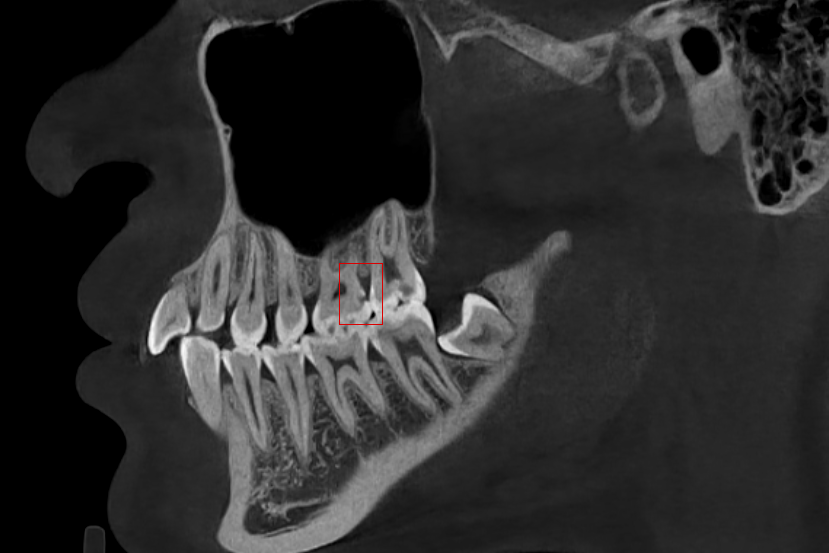

根尖炎病理分析